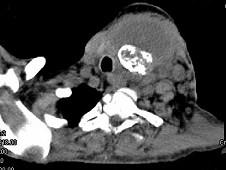

问题 女,64岁,发现双甲状腺肿大一月余,CT如图所示,最可能诊断为 ( )

选项 A、甲状腺转移瘤 B、甲状腺结核 C、甲状腺腺瘤 D、甲状腺癌并淋巴结转移 E、结节性甲状腺肿

答案 D